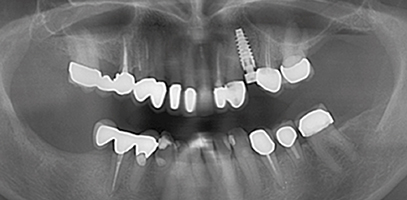

Een 72-jarige dame meldt zich op verzoek van haar tandarts voor een specifiek consult. Zij heeft in de bovenkaak twee problemen:

De brug in het eerste kwadrant heeft een probleem aan de voorste pijler: de kroon op de 15 zit los en lekt (afbeelding 1 - 3 ). De verwijzend tandarts vraagt om advies.

Occlusaal aanzicht van de bovenkaak

Het implantaat dat geplaatst is in het tweede kwadrant staat volgens de verwijzer niet goed in de boog. Er is geen ruimte om een kroon op dit implantaat te plaatsen zonder de kronen op 23 en 25 te beschadigen (afbeelding 4 ).